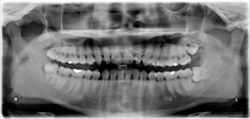

The upper left (picture right) and upper right (picture left) wisdom tooth are distoangularly impacted. The lower left wisdom tooth is horizontally impacted. The lower right wisdom tooth is vertically impacted (unidentifiable in orthopantomogram).